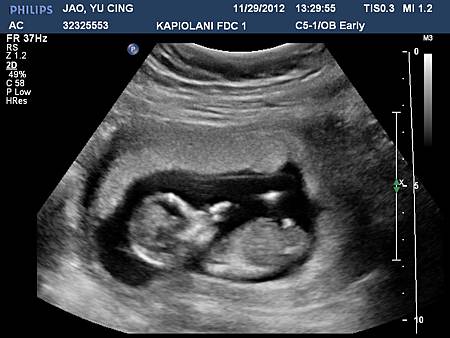

11/29 再次到蔡醫師的診所報到~ 今天還要到Kapiolani 婦幼醫院做高層次超音波跟抽血驗down syndrome

原本蔡醫生說今天做的超音波是3D的~ 我們還興奮了一下~ 不過後來看好像還是只有2D啊

不過可以看到寶寶就很開心了啦 哈哈~ 這次更有人樣了耶!!! 還看到他在吸手手~~ 真的好可愛